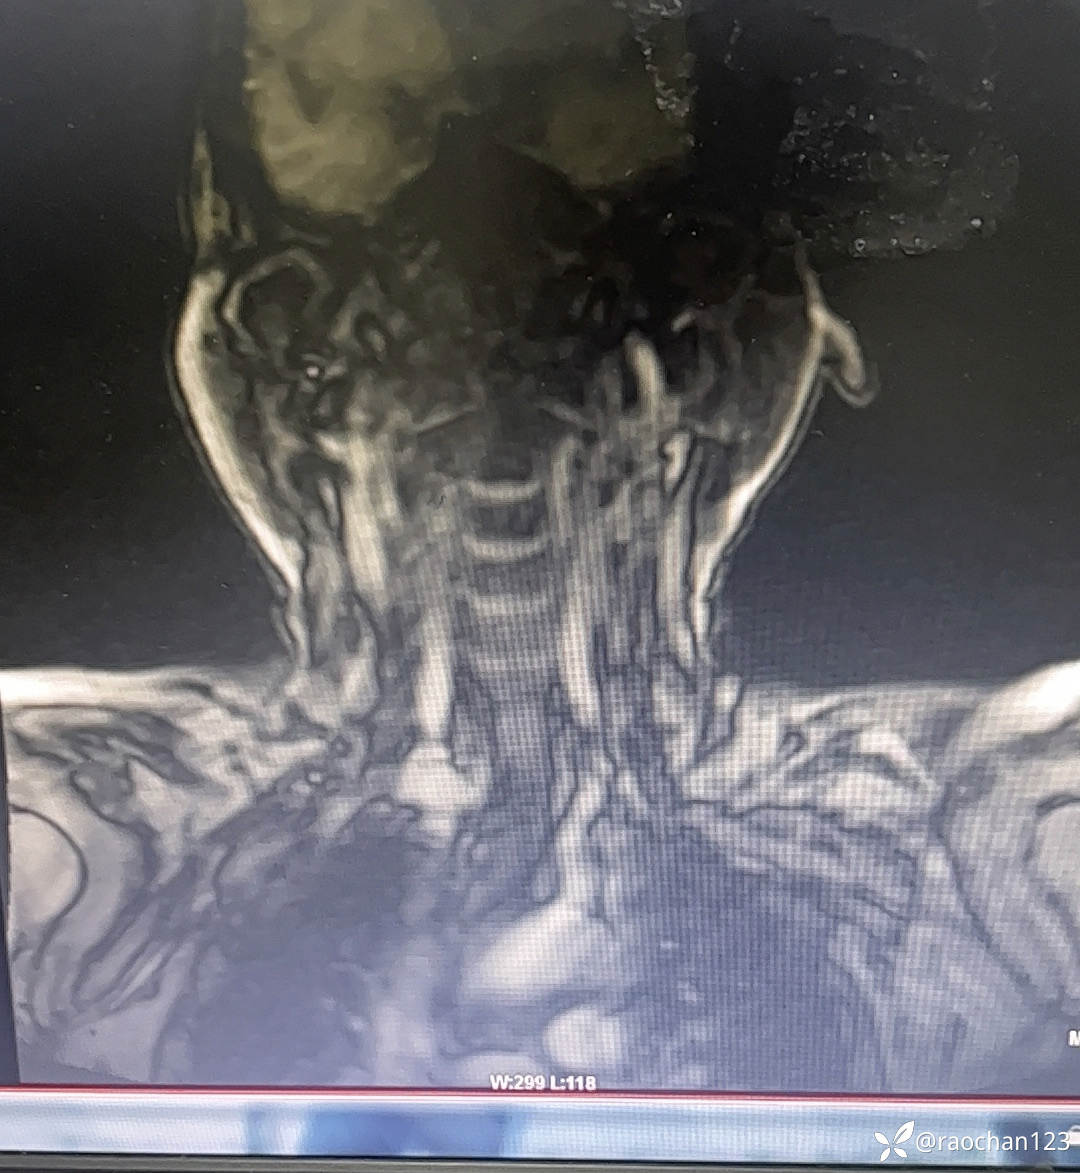

【治疗经过及结果】:给予低流量吸氧,布洛芬混悬液 解热 镇痛,左氧佛沙星抗炎(既往有头孢过敏史)、止痛,热毒宁注射液 清热解毒;艾箱灸、中药塌渍、中药涂擦、火罐、TDP、中药热奄包等中医外治通络祛痛等治疗后,仍有发热,肌酸、肌痛、关节疼痛症状。复查血常规:2024-11-8 13.93# 谷丙转氨酶 45U/L 天门冬氨酸 25U/L 白蛋白 27.0g/L 进一步查乳酸脱氢酶 284U/L 肌酸激酶 26U/L,PCT 0.44ng/ml BNP 811ng/L 免疫五项中IgGA 5.38g/L 血钙 1.94mmol/L 尿微量白蛋白 32.2mg/L 25羟基维生素D 22.68ng/ml 甲胎蛋白、癌胚抗原(-)。颈椎MRI:1.颈椎骨质增生,C4/5、C5/6、C6*7椎间盘轻度突出2、颈后皮下软组织内脂肪堆积,请结合临床。(后颈部皮下软组织内可见异常信号影,T1T2呈高信号,压脂序列呈低信号,颈椎生理曲度变直,椎体后缘连线尚连续,椎体缘骨质光滑,各椎间隙未见狭窄,椎体信号欠均匀,部分椎间盘T2信号减低,C4/5、C5/6、C6/7椎间盘向后轻度突出,硬膜囊轻度受压,椎管无狭窄,黄韧带无肥厚,颈隋未见明显异常)。骨密度:骨质疏松(T值 -4.2)。抗ANA抗体 RF 抗CCP抗体 ENA抗体谱结果待回。患者服用布洛芬混悬液后出现大汗淋漓,血钙偏低,调整为停服布洛芬混悬液、给予醋酸泼尼松10mg 2次/日 口服 解热、抗炎、止痛,金钙尔奇 600mg 2次/日,骨化三醇 0.25ug/日 口服 改善骨质量,暂给予肠内蛋白营养(患者饮食无异常),余治疗同前。